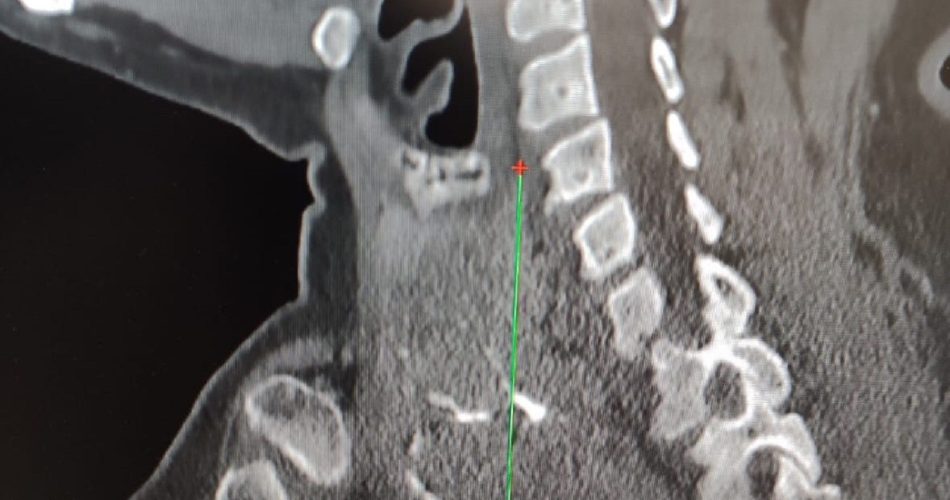

estensione gozzo tiroideo

Un intervento complesso e raro è stato eseguito con successo al Policlinico di Bari su una paziente di 65 anni affetta da un gozzo plongeant (o endotoracico), una forma di ingrossamento della tiroide che si estende fino al torace. La massa, di circa sette centimetri, comprimeva le strutture circostanti e aveva già causato alla donna una forte riduzione della voce.

L’operazione di tiroidectomia è stata condotta dalle équipe di Otorinolaringoiatria e Cardiochirurgia, che hanno lavorato in sinergia con l’anestesista. Il gozzo, infatti, si era spinto fino al mediastino – la parte alta del torace – deviando la trachea verso sinistra e arrivando a coprire le corde vocali.

“Gli accertamenti radiologici hanno mostrato una tiroide ingrandita con noduli e calcificazioni, che si estendeva nel torace comprimendo le strutture vicine. Per la rimozione è stato necessario un approccio sternotomico, cioè l’apertura parziale dello sterno, grazie al supporto dei cardiochirurghi”, spiega il dottor Luigi Madami, otorinolaringoiatra dell’Unità operativa diretta dal professor Nicola Quaranta.